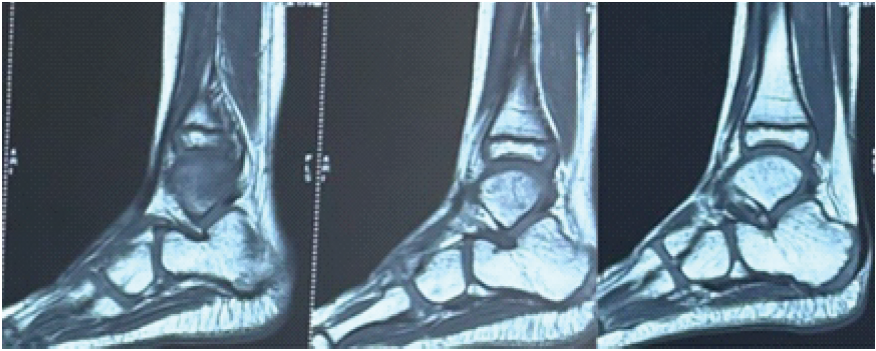

Bony biopsy, synovial biopsy samples sent for acid-fast bacilli (AFB) stain, tubercular cultures, and Cartridge-Based Nucleic Acid Amplification Test (CBNAAT) were all negative. The material that was sent for culture sensitivity grew P. aeruginosa. ATT was stopped. Culture-specific antibiotics for Pseudomonas were started. At present, around 10 months post-biopsy and drainage, he was walking without any pain and full weight bearing. X-rays at 10 months showed a healing lytic lesion of the fibula (Fig. 4). MRI showed resolution of synovitis: Joint effusion and marrow oedema (Fig. 5).

Figure 5: Magnetic resonance imaging 10 months postoperatively showing resolved synovitis and no marrow edema.